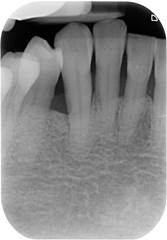

牙周病治療前、後的差別

(x光)

治療前

齒槽骨有缺角性的破壞

治療後

缺角性的骨破壞經牙周

再生手術後獲得填充